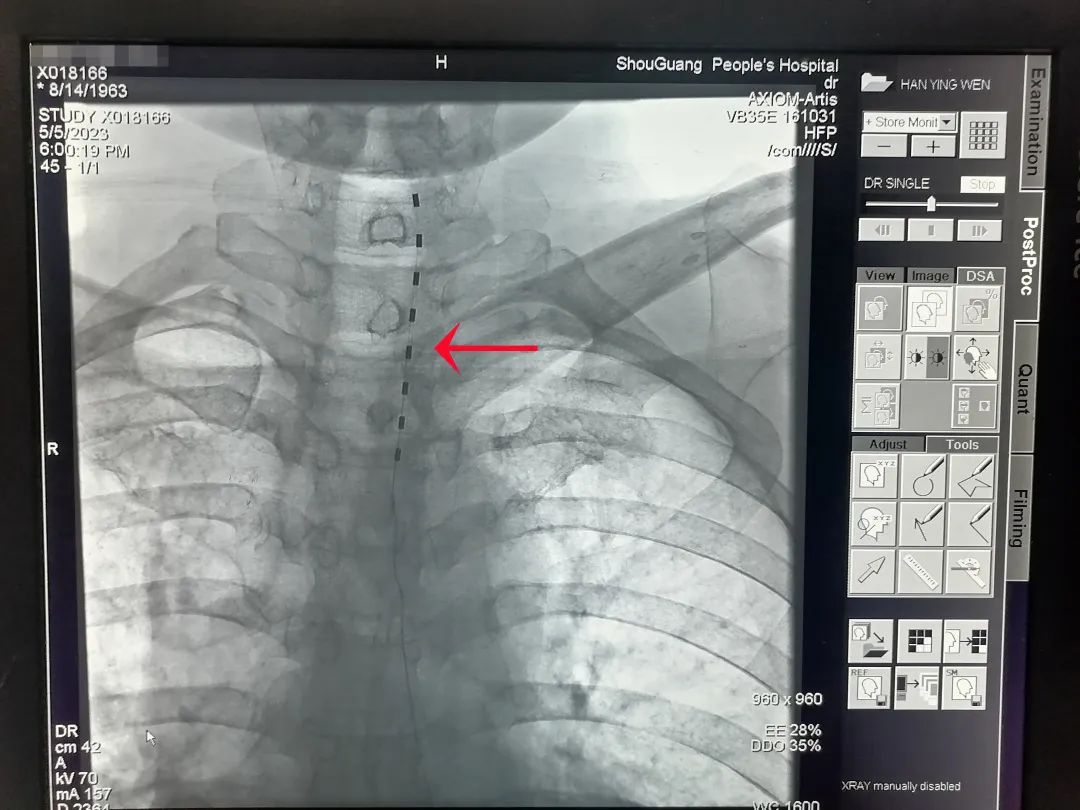

椎管内植入的刺激电极

脊髓神经电刺激疗法是将电极植入脊柱椎管内,以脉冲电流刺激脊髓神经,阻断疼痛信号通过脊髓向大脑传递,使疼痛信号无法到达大脑皮层,从而达到控制疼痛的目的,是目前国际上公认的治疗慢性顽固性疼痛的先进疗法。它的成功开展,为慢性顽固性疼痛患者的治疗提供了一种新的、有效的治疗途径,为此类疾病患者带来了巨大福音,使无数慢性顽固性疼痛患者摆脱了疼痛的困扰。